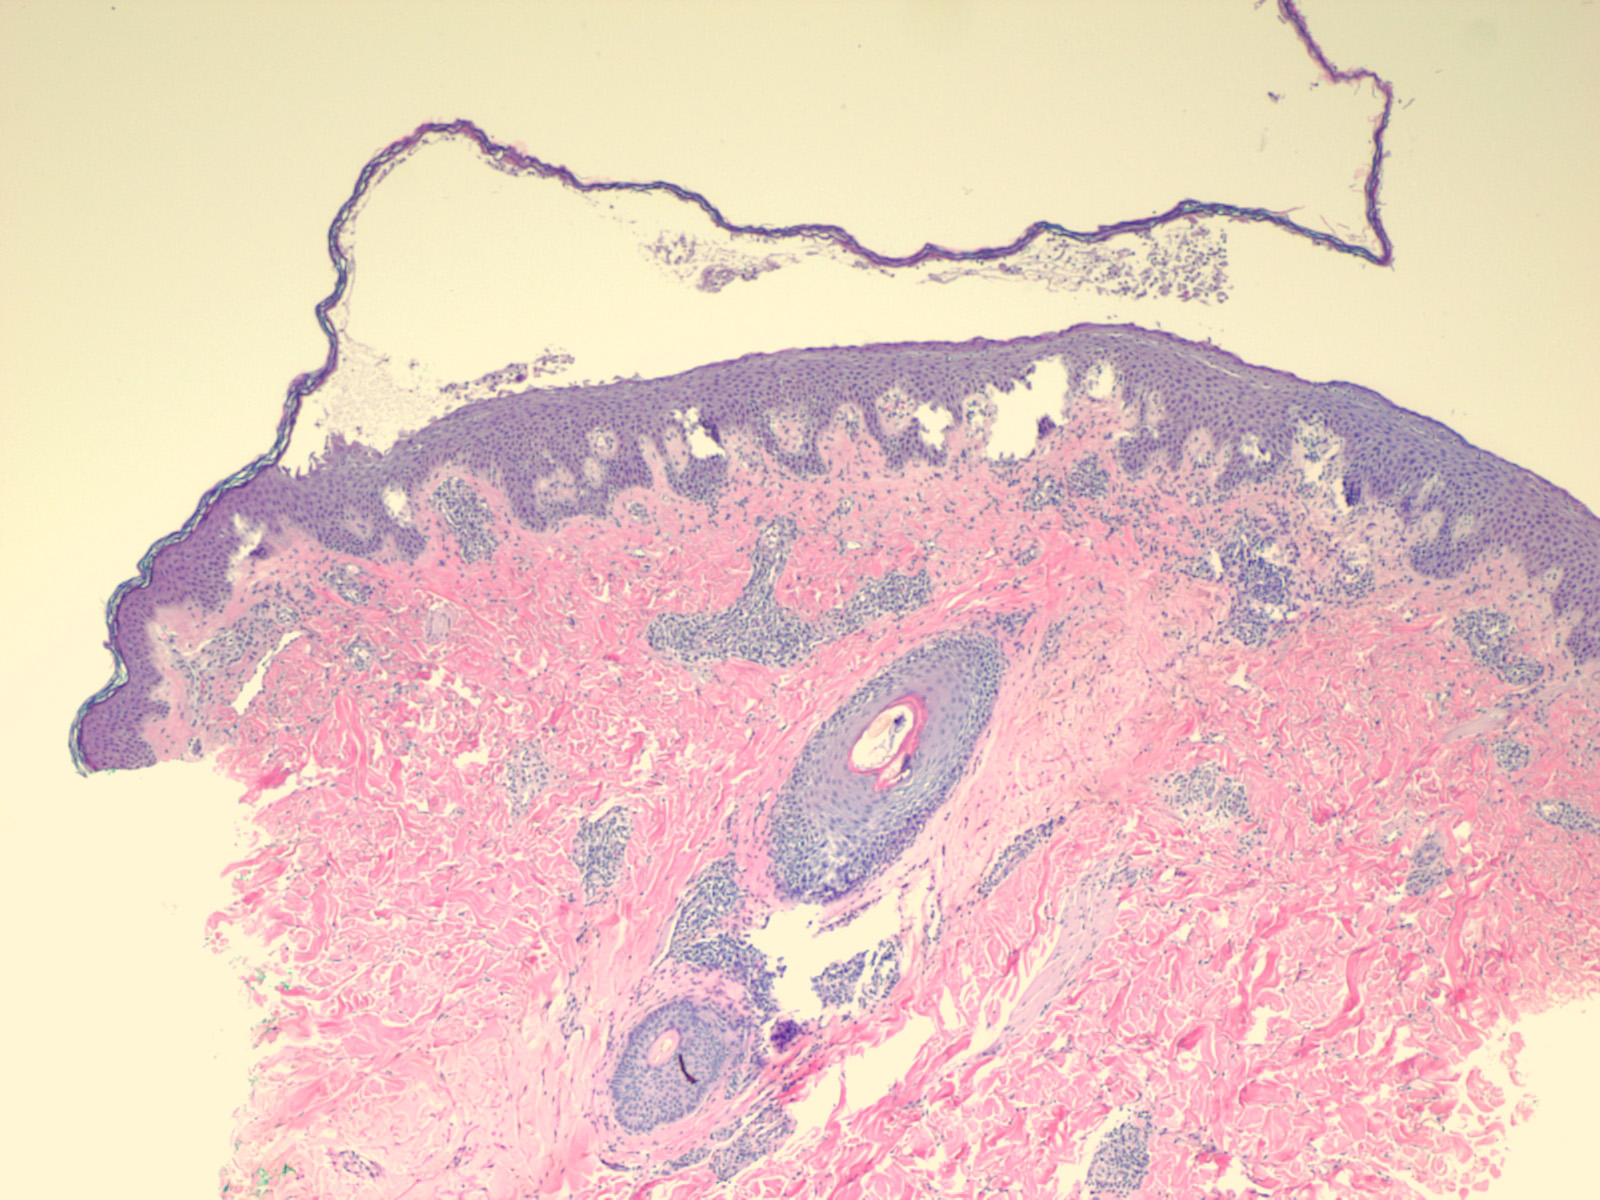

Staphylococcal scalded skin syndrome = متلازمة الجلد المسموط بالعنقوديات